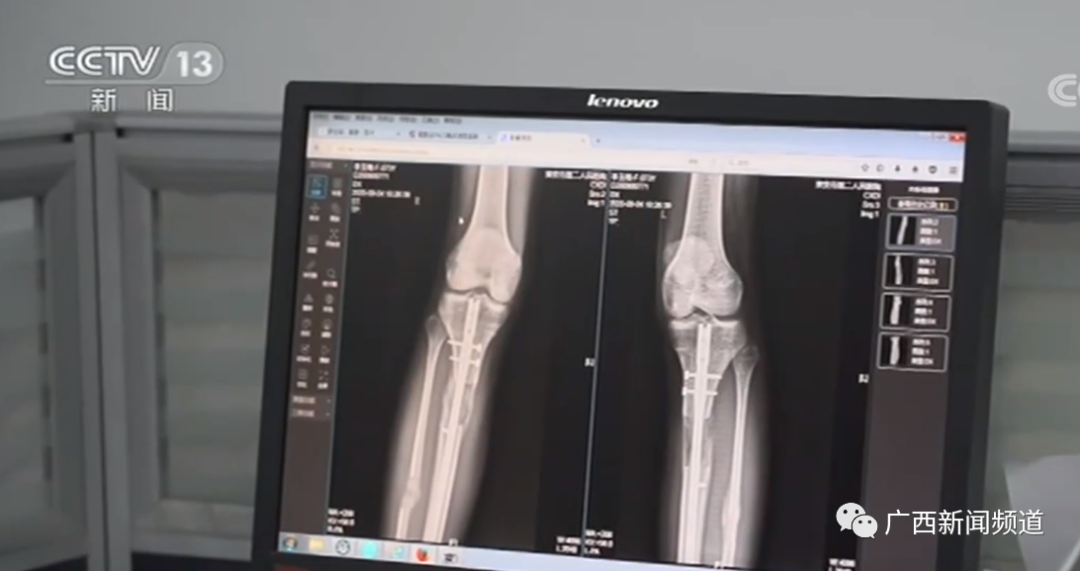

此外,“断骨增高”也是许多人耳熟能详的所谓“长高捷径”,甚至被一些人视为成年后的“救命稻草”。2020年央视曾报道,江苏淮安一名22岁的小伙因为对身高不满,在国外做了断骨增高手术,却致双腿严重感染、无法行走,甚至可能终身残疾。而我国2006年就已明确规定,断骨增高手术严禁用于美容项目。